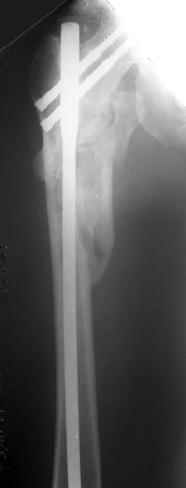

Другое наблюдение:Мужчина, 1957 г.р. Травма в результате ДТП 12.09.04г.

Диагноз: Закрытый оскольчатый подвертельный перелом правой бедренной кости со смещением отломков, оскольчатый перелом большого вертела, отрывной перелом малого вертела.Сопутствующие заболевания: Язвенная болезнь желудка, ремиссия.

Наверно, можно и так сказать, но можно и тоже самое - 4-фрагментный вертельный перелом. Выбор тот же, но с учетом молодого возраста реконструкционный гвоздь тут более применим. Вот уже наш пример.

Перелом подвертельный. Лечение оперативное, срочное,

PFN с длинной ножкой чтобы избежать стрессовые изменения в будущем. Обычно у молодых людей требуется проводить рассверливание канала как при гвоздевании.

полную нагрузку через 6 недель т.е. после образования костной мозоли, что позволить более или менее сохранить длину шейки.